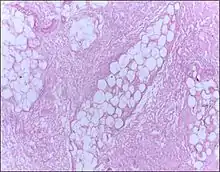

![]() | Fat necrosis | Breast lump showing an area of fat necrosis showing shadowy outlines of necrotic adipocytes surrounded by an inflammatory reaction with cholesterol clefts. | Category: Histopathology of liponecrosis | Liponecrosis |